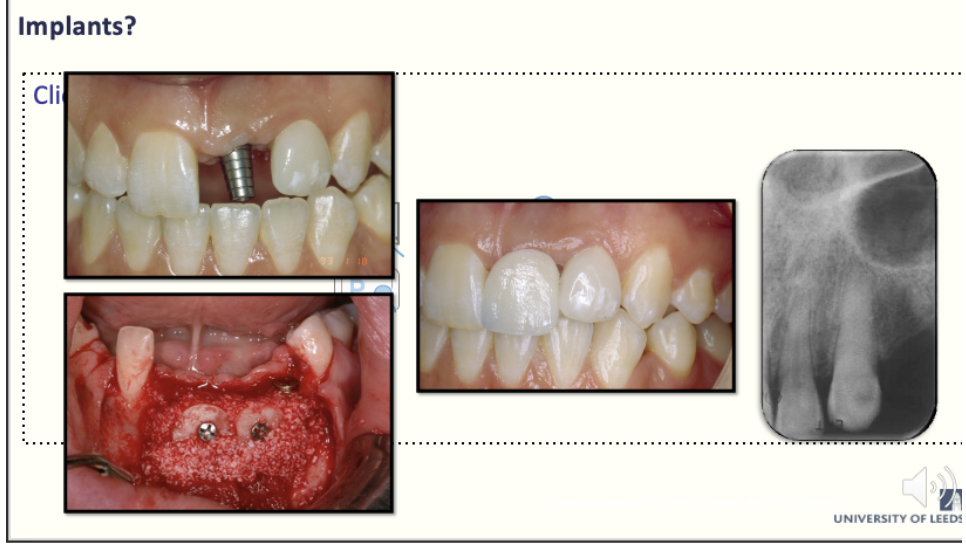

What are implants

The implant may be a gold standard for missing tooth

- The only replacement for root and relies on excellent lab word and clinical work for the restoration

- May have insufficient bone for the implant

- Surgery may provide more bone for certain circumstances